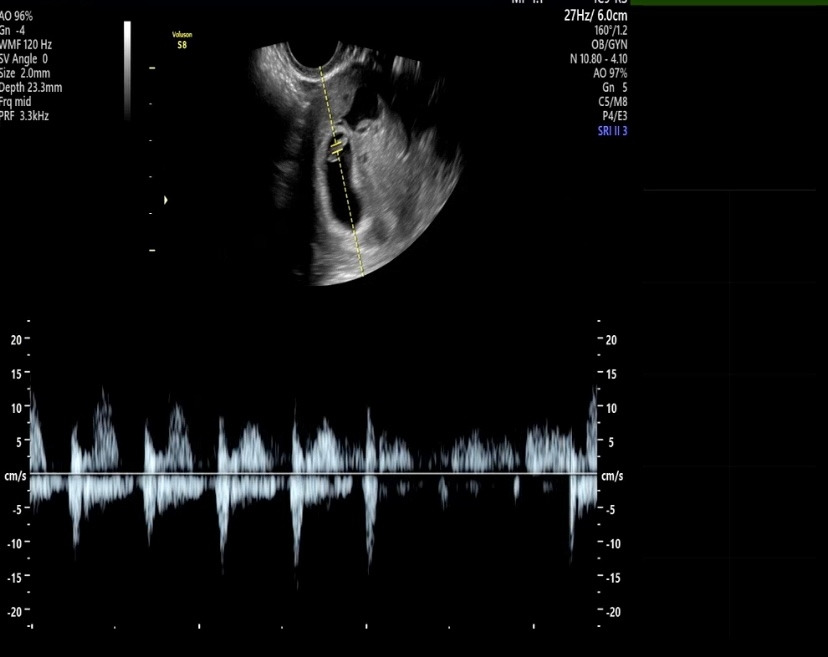

이전 02화심장소리를 들었다